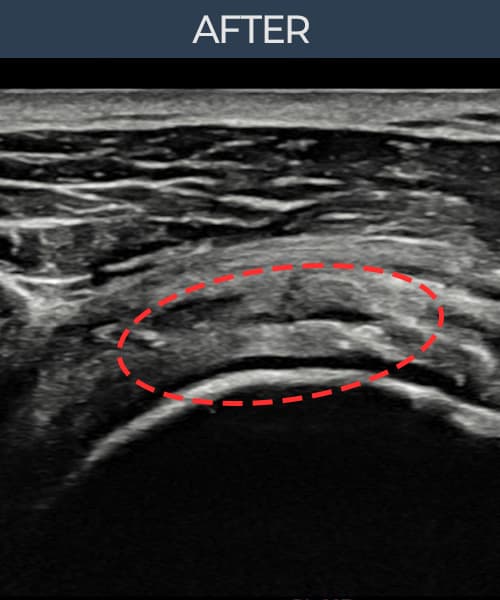

[経過期間: 23.07.31~23.09.27]

[縫縮術] 超音波検査にて左 棘上筋腱 부착부 광범위 部分断裂(13mm × 5mm (腱厚の約65%欠損))を確認。縫縮術施行後、腱の連続性が回復し、日常生活に復帰されました。